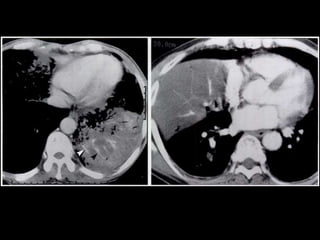

o Pleural involvement

§ Common: 10%

§ Hemorrhagic effusion denotes direct tumor invasion

§ Effusion carries a poor prognosis even if no malignant cells are found